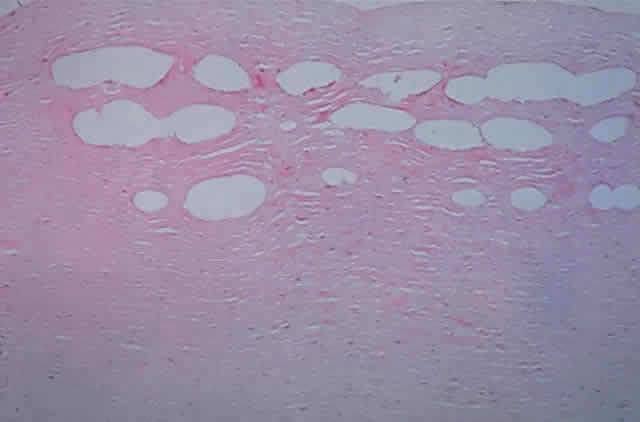

Using animal and bank eyes, the author has demonstrated the ability to create fine layers of cavities, with the desired degree of spacing or overlap, in a controlled fashion (Fig. 9). Electron micrographic studies demonstrate little collateral damage at the ablation surfaces. Other investigators have also demonstrated the ability to produce ablation cavities that lead to a secondary deformation of the anterior cornea, although unpredictably. However, there is no evidence to date that one can achieve a desired deformation of a primate cornea with Bowman's membrane, let alone with any desired degree of accuracy. However, the novelty of this approach is exciting, because the anterior cornea is left undisturbed and a mechanical microkeratome is not needed. This would be a procedure with no pain, rapid visual recovery, and possibly reduced complications. Concerns remain over the effect of the shock waves produced on various aspects of the eye, especially the endothelium, although studies to date demonstrate no endothelial damage if the cavities are kept in the anterior stroma.

Fig. 9. Intrastromal photodisruption by Novatec laser.